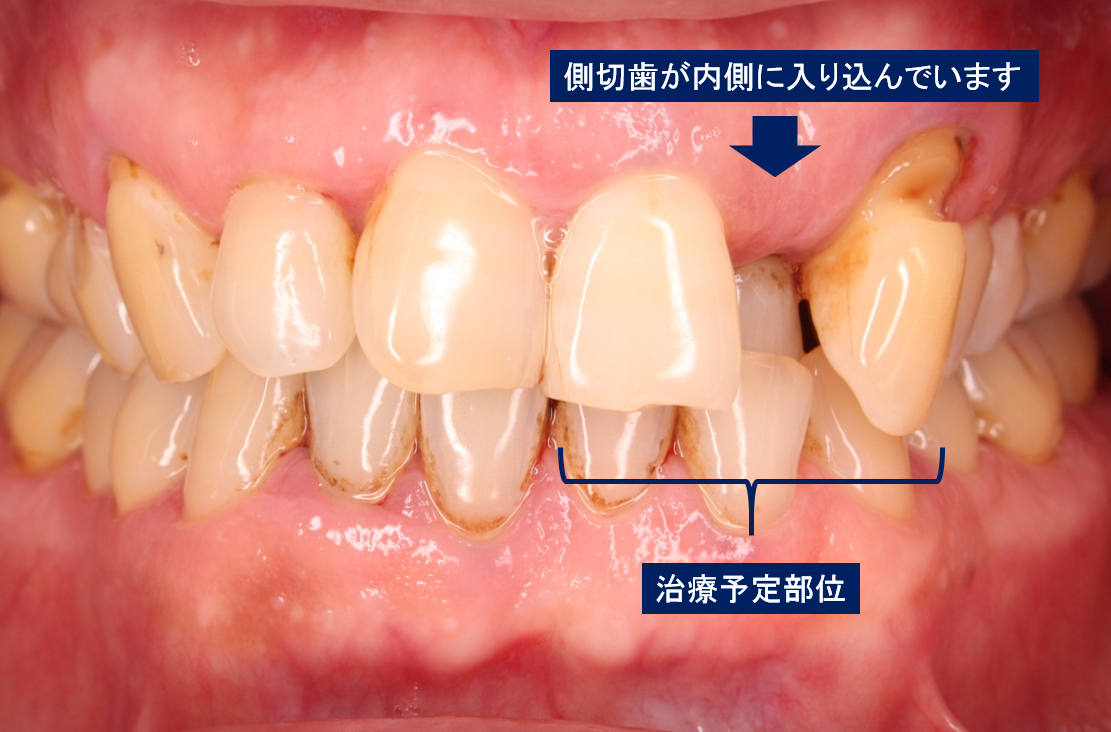

ワンランク上の審美治療

こんにちは。 南館歯科クリニックの木村です。 左上の前歯の治療ケースをご紹介します。 50代男性です。 初診時 左上の前歯の審美障害を改善したいとの希望があり、ご本人はイン…

綺麗になりました。

こんにちは。 南館歯科クリニックの木村です。 40代の女性のケースをご紹介します。 治療前の左側面観 いままで何度も治療を繰り返し受けてきたそうですが、このままでは自分の歯がダメになるの…